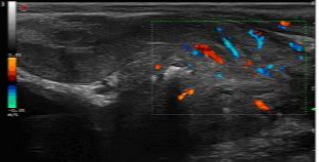

造影谐波成像Ultra-CnTI

通过对发射脉冲频带及能量的精确控制,使脉冲最佳的匹配造影剂微泡的非线性响应,从而获得纯净、丰富的、超强的造影剂回波信号:HFRI 高帧频动脉关注成像-更好的造影动脉相CCPI编码造影成像-利用编码成像原理进行发射和接,提高深部组织的造影穿透力DCTI造影三频段接收技术-提高造影剂检测灵敏度,更少的造影剂用量DP声压精控技术-可最大限度的保护微泡,减少微泡破裂,保证持续的、清晰的造影剂灌注观测,可进一步提高对造影微泡敏感的检测,具有更好的造影延迟相全身应用,尤其高频造影更为显著-腹部、高频、心脏、腔内、术中探头均支持造影功能,具有造影双幅动态显示和一键转换调节功能,造影动态图像连续长时间不间断采集;

术前诊断

术后评估